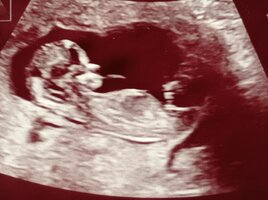

Nub-teorian mukaan sukupuolen voi määrittää jo nt-ultrassa genitaalikyhmyn asennon perusteella. Voit lukea aiheesta lisää täältä.

Kiinnostaako teitä sukupuolen määrittäminen kyseisen teorian avulla? Katsotteko ultrakuvia sillä silmällä?

Kiinnostais kyllä ja ite en ainakaan tajunnut tuosta nt-ultran kuvasta mitään..